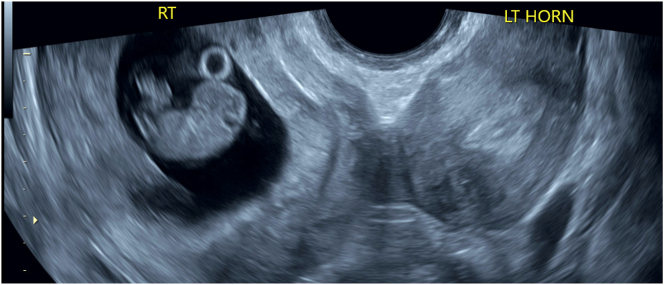

Case presentation: Our patient is a 32-year-old G4P1021 (Gravida 4 Para 1,021-1 term delivery, 0 preterm deliveries, 2 abortions, 1 living offspring) who presented at 8 weeks of gestation with a known history of a didelphys uterus. Her obstetrical history was significant for a prior low-transverse cesarean section at term. All four of her pregnancies were located in the right uterine horn. At 39 weeks 3 days of gestation she presented in early labor and requested a TOLAC. She received an epidural, a cervical ripening balloon was placed, and she was started on pitocin. She pushed to deliver a viable infant. The patient's postpartum course was uncomplicated, and she was discharged home on postpartum day two.